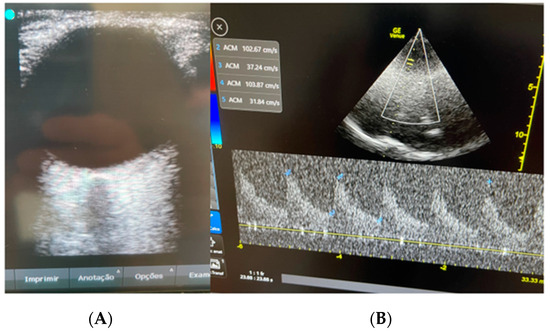

| Date | CSF | ONSD | TCD | B4C |

|---|---|---|---|---|

| D 0 | Pan-herpes negative | |||

| Day 2 | 5.6 mm | MCA 59 cm/s; PI 1.2; RI 0.7 | P2 > P1 | |

| Day 2 | MCA 65 cm/s; PI 1.0; RI 0.5 | P1 > P2 | ||

| Day 5 | Pan-herpes negative |